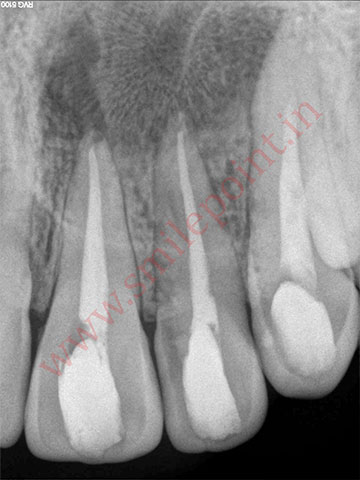

Gum Care Surgery